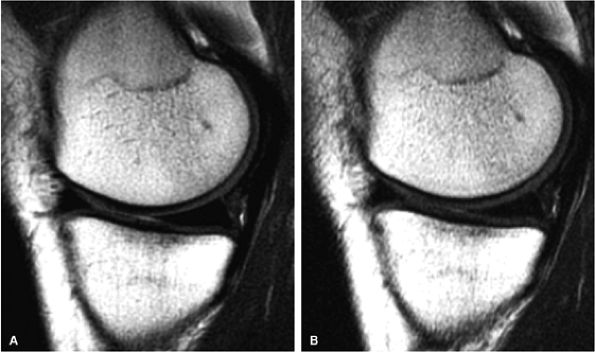

FIGURE 1.5 ● (A) PROPELLER fast spin-echo with a 480 × 480 matrix. (B) Conventional 2D fast spin-echo with 480 × 384 matrix. Scan times were identical. Note an apparent SNR gain in (A) as well as better delineation of cartilage and menisci.